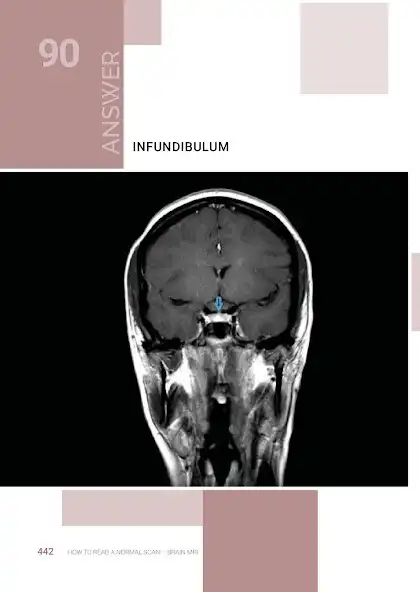

This is an exciting and easy to use Atlas / Quiz of NORMAL Neuroradiology, and attempts to bridge the gap between Anatomy atlases and Radiology atlases. It focuses on the needs of neurology residents and medical students, but anyone who is interested in the radiological anatomy of the brain will find it useful. Using these books as android apps is also reducing production cost , saving printing cost (and trees too in case you like trees). But these same books are also available elsewhere as print versions, but for higher cost.

The objective of the How to Read a Normal Scan series is to familiarize you with NORMAL anatomy as seen on MRI scans and CT scans before memorizing what Hallevorden Spatz or Blah

Blah looks like (sure enough in your Board exam they will want you to identify Blah Blah that no one has seen in 500 doctor years). My hope is, that after reading these books, at the very least you can point out structures on a normal scan and identify exactly what they are. And it is not just about avoiding the embarrassment of ignorance, it is about the sheer satisfaction of knowing what these things are.. If you notice any errors please reach out to me and I will be sure to fix it in the next edition.